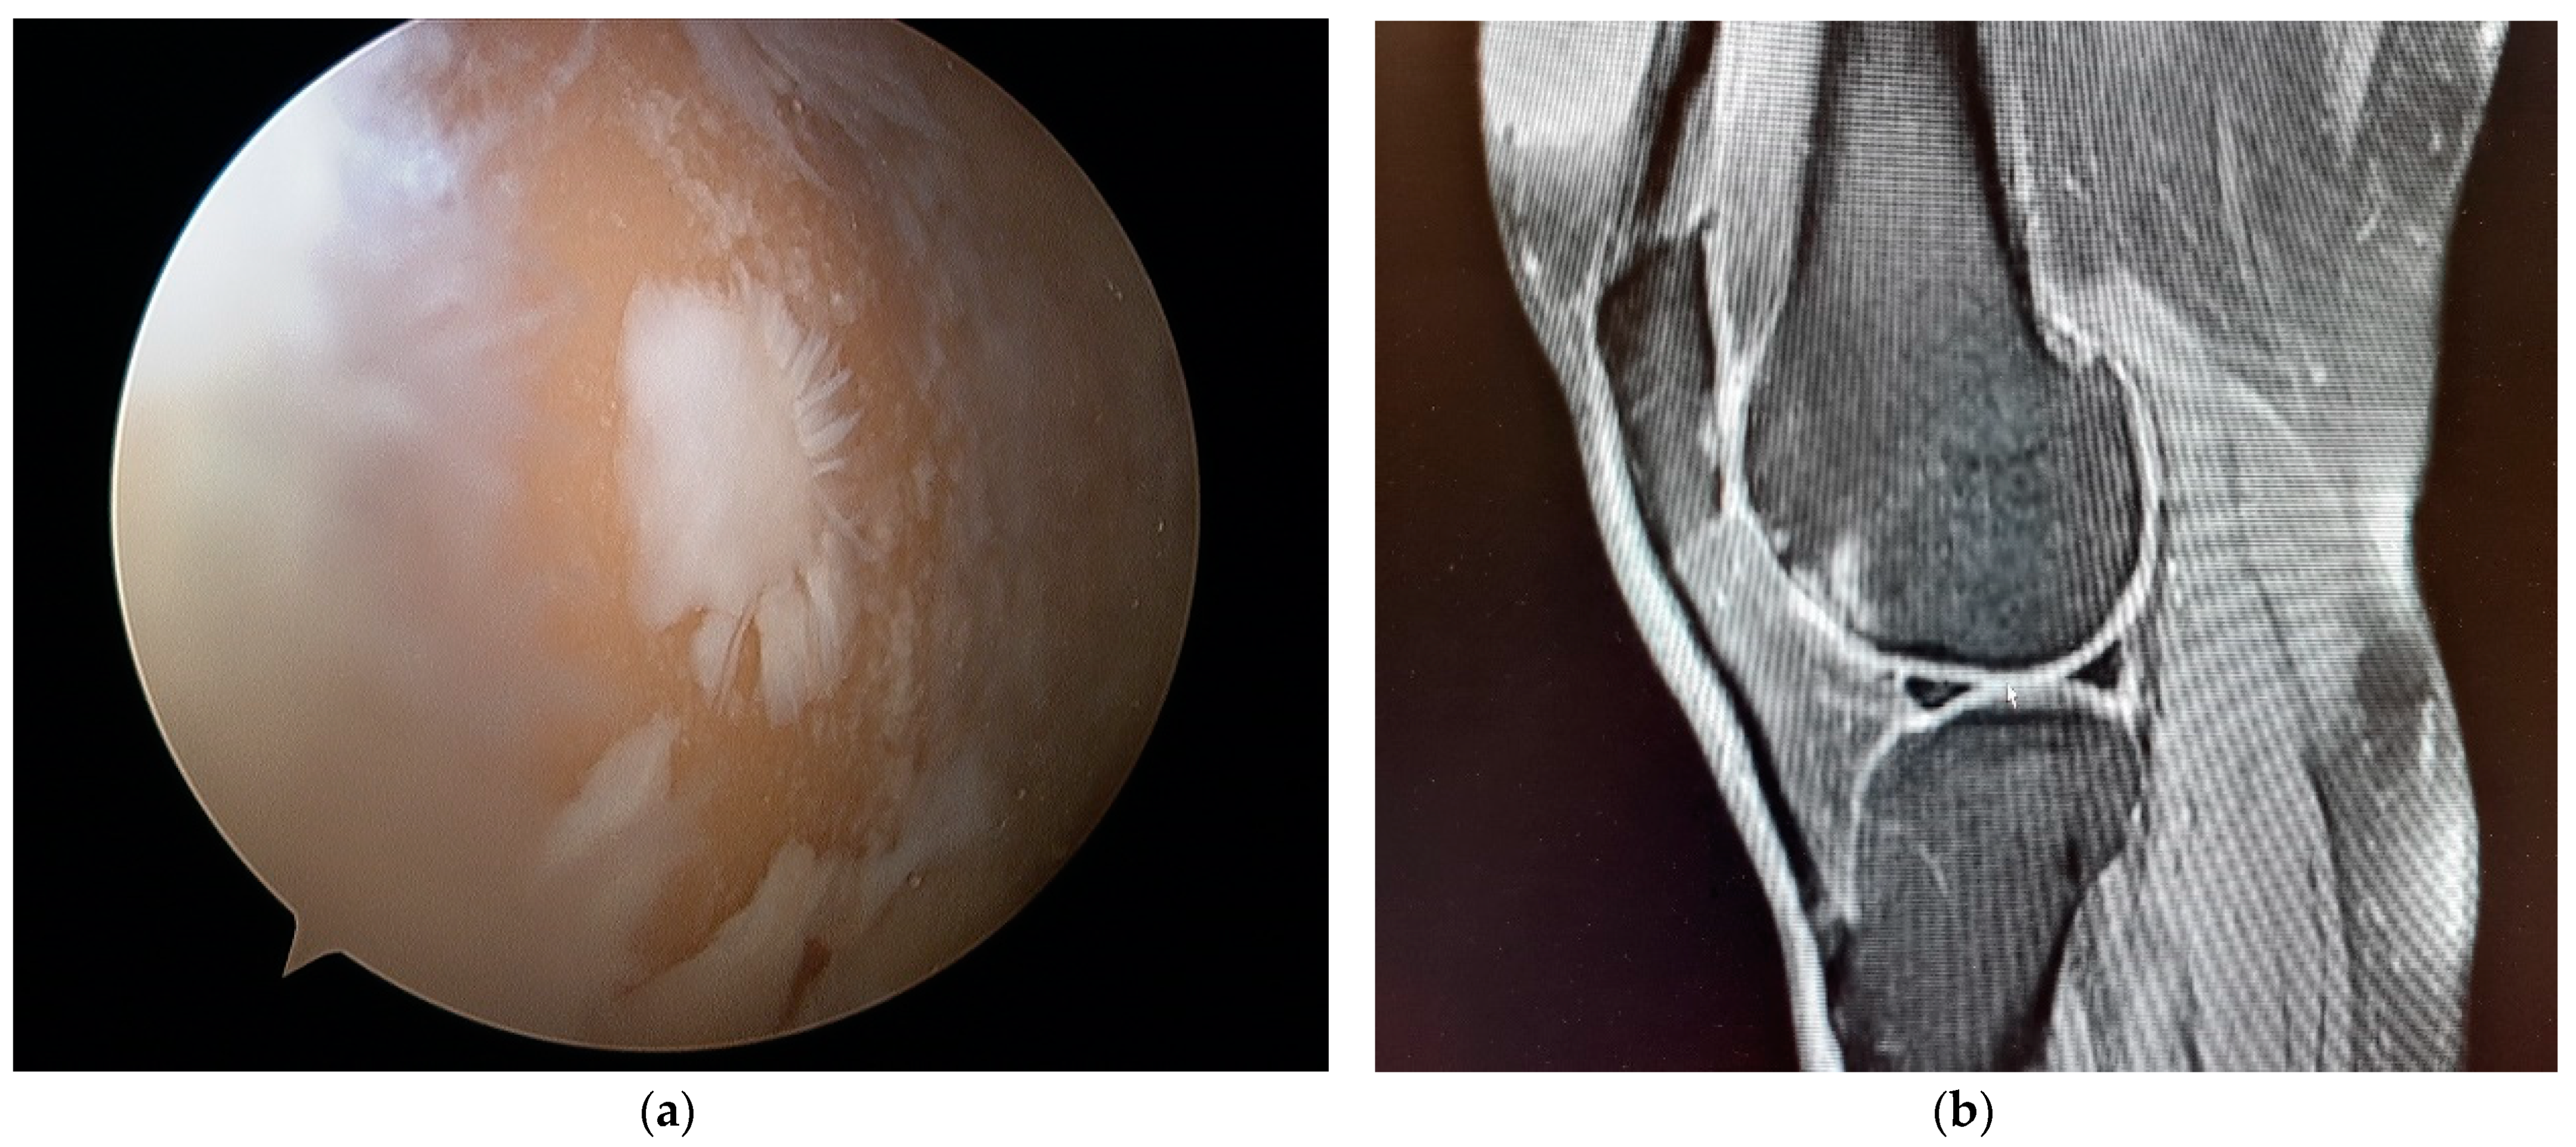

2. Materials and Methods

3. Results

4. Discussion